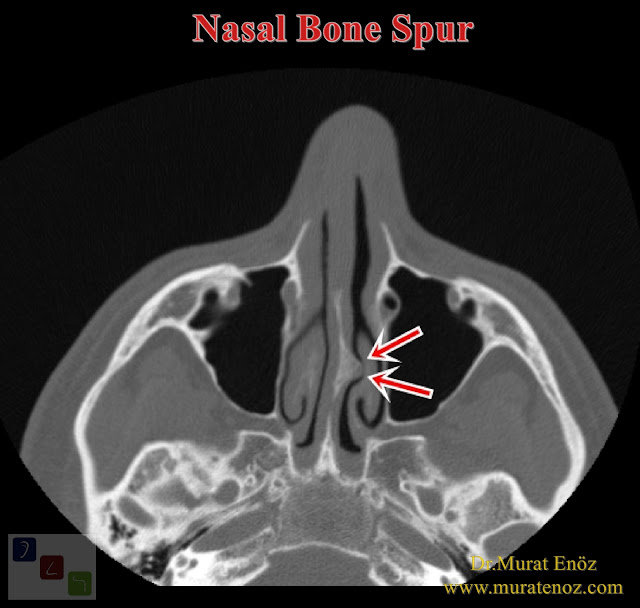

From www.ent-istanbul.com

Ossified Overhang (Osteophyte) In The Nose That Can Cause Atypical What Does A Nasal Bone Look Like On Ultrasound The nasal bone is a small, flat bone located in the upper part of the nose. The nasal bones are small paired oblong upper central facial bones placed side by side between the frontal processes of the maxilla, jointly forming the nasal ridge. Babies with down syndrome (also known as trisomy 21) have noses with flat bridges, and nose bones. What Does A Nasal Bone Look Like On Ultrasound.